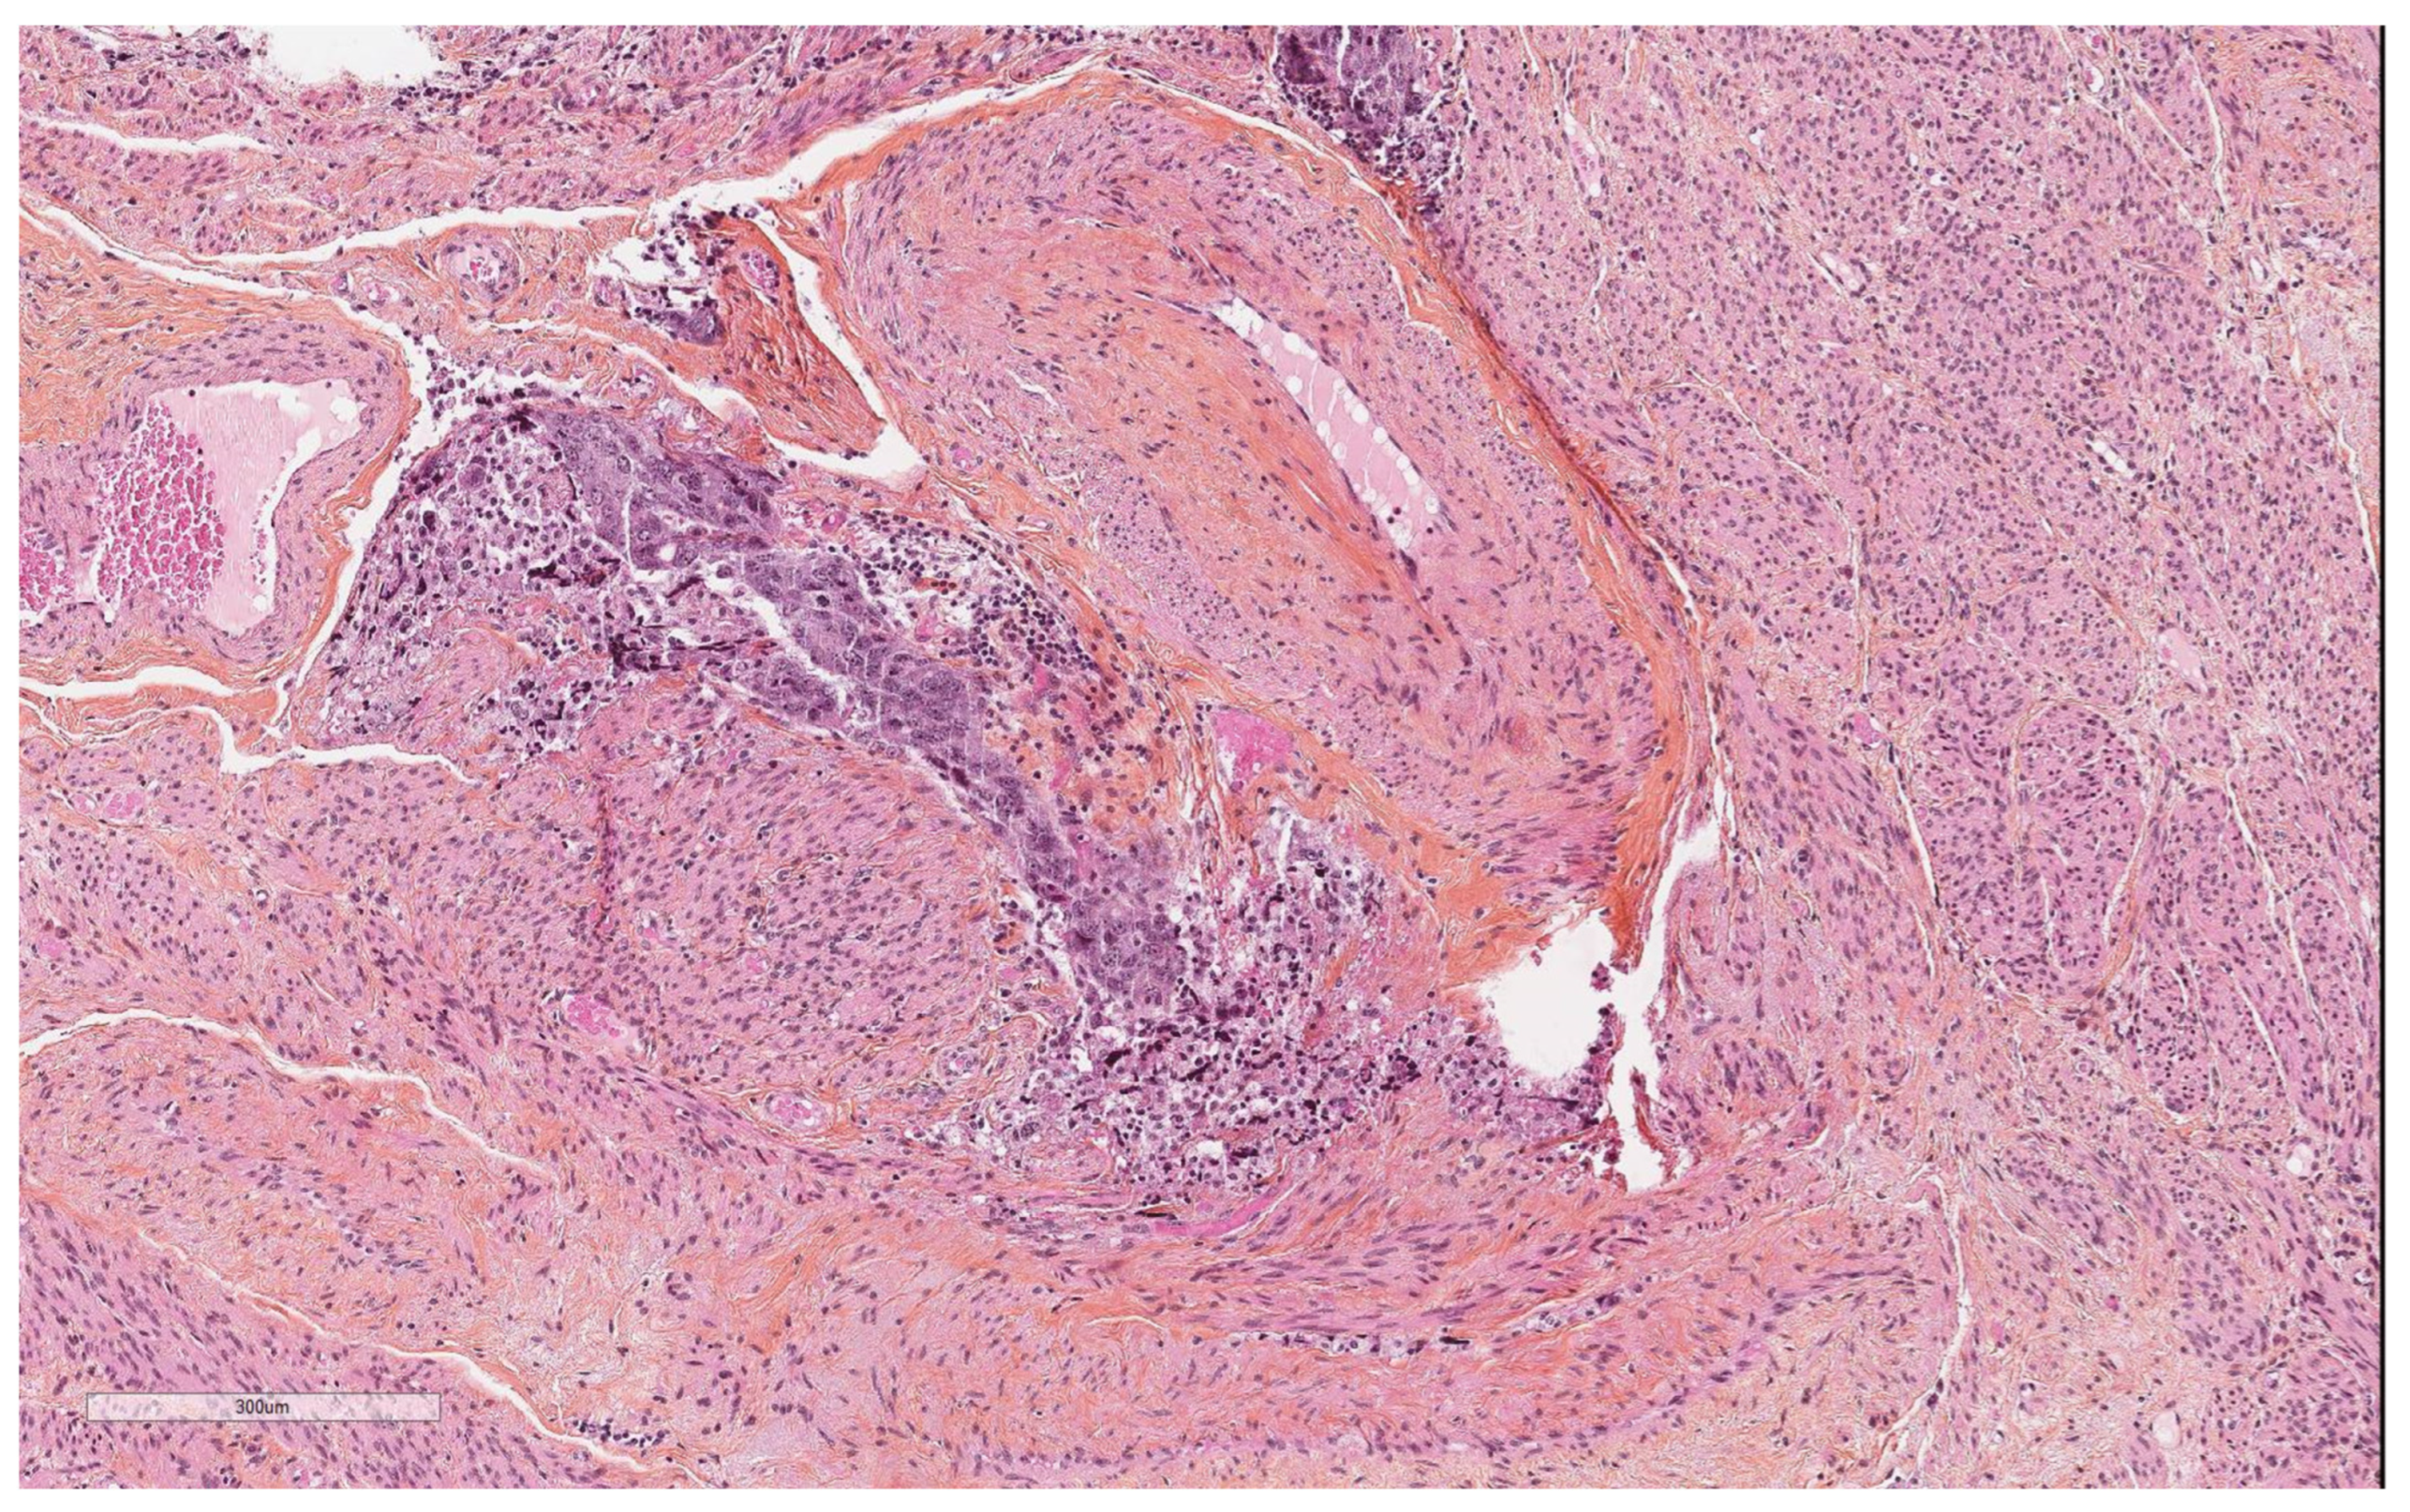

| Vascular pseudoinvasion | |

| Present | 14 (23.7) |

| Absent | 46 (76.6) |

| Cells in the cervical lumen | |||

| Present | 7 | 7 | 0.013 |

| Absent | 7 | 38 | |

| Uterine pathology | |||

| Malignant | 13 | 20 | <0.001 |

| Benign | 1 | 26 | |